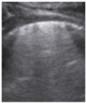

- Subpleural consolidation <1 cm (Figure 4a,b)—31.57%;

Figure 4. (a) The lung ultrasound showed a small consolidation area with the length <1 cm corresponding to a LUSS = 2; (b) The CT exam revealed bilateral consolidations in the posterior segments. - Pleural effusion—5.26%.